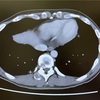

【CT結果】頭部、肺、肝臓の転移状況

さて、CTの結果ですが、主治医の先生から下記の通り、お話がありました。

【主治医のCT評価】

・脳転移

悪くなっていない。癌自体は変化がないものの周囲のむくみは取れてきていて、痙攣などを落ち着いているのではないか。画像を見るとなんとなく癌も薄くなっているかも(あまり期待はしてはいけない)。

・肺転移

こちらも現状維持。大きくなっていない(悪化していない)。スチバーガが効いている可能性あり。画像を見ると癌に空洞化も見える。

・肝転移

問題は肝臓の転移。思ったよりも進行が早く、肝臓の1/4くらいまで癌細胞が大きくなっていました。これ以上大きくなると胆嚢を圧迫してしまうので進行しないように注意が必要。

・治療方針

脳、肺の進行は落ち着いているからよかった。肝臓は対処が必要。今日はスチバーガを継続して、次回点滴に切り替える決断する必要があるかも。

ということで、スチバーガは継続して、次回は9月中旬にまた次の治療方針の相談となりました。